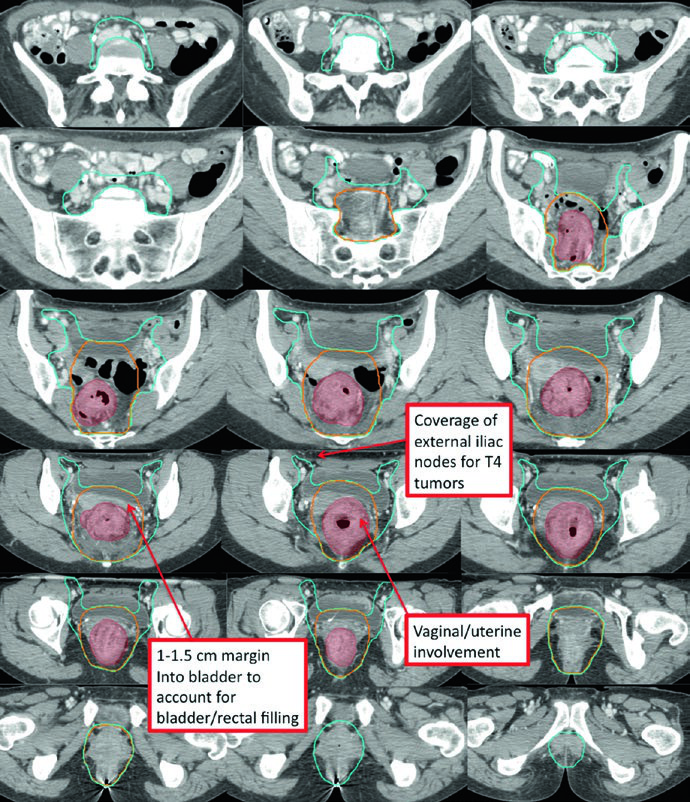

O CTV de risco padrão (CTV-SR) cobre o CTV-HR completo, todo o mesorreto e os linfonodos ilíacos internos bilaterais. A inclusão dos linfonodos ilíacos externos e obturadores bilaterais é obrigatória para tumores T4 com envolvimento de órgãos anteriores (bexiga, cérvix, próstata). Se o tumor primário se estende inferiormente para o canal anal, os linfonodos ilíacos externos e inguinais bilaterais devem ser incorporados ao CTV-SR.

| CTV-SR | CTV-HR + mesorreto completo + linfonodos ilíacos internos bilaterais. Ilíacos externos e obturadores para T4 com invasão anterior. Inguinais para tumores com extensão para o canal anal. Superior: interespaço L5/S1 ou 2 cm acima da doença macroscópica. Inferior: assoalho pélvico ou 2 cm abaixo da doença. Margem de 0,7 cm ao redor dos vasos ilíacos internos. Margem anterior de 1-1,5 cm na bexiga |

A doença T4 com invasão de órgãos anteriores amplia significativamente o volume de tratamento. Nesse cenário, o CTV-SR precisa cobrir a região dos linfonodos ilíacos externos, e a margem anterior dos campos laterais deve ser ajustada para pelo menos 1 cm anterior à sínfise púbica.

| Pelve inferior | Inferior: 2 cm abaixo da doença macroscópica, incluindo todo o mesorreto até o assoalho pélvico. Lateral: poucos mm além dos músculos levantadores, exceto se há extensão tumoral para a fossa isquiorretal. Margem de 1-2 cm para áreas de invasão em tumores T4 |

| Pelve média | Inclui reto, mesorreto, região dos ilíacos internos e 1 cm de margem na bexiga. Posterolateral até musculatura ou osso da parede pélvica. Anterior: pelo menos 1 cm na bexiga posterior. Margem de 7-8 mm em tecido mole ao redor dos vasos ilíacos internos |